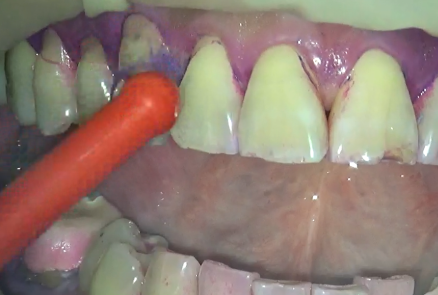

ということで、今回は、歯間ブラシとワンタフトブラシを使用していきます。

三か所、ピンポイントで磨いてみましたが、

状況にあった道具を使うと簡単にプラークは落とす事が出来ます。